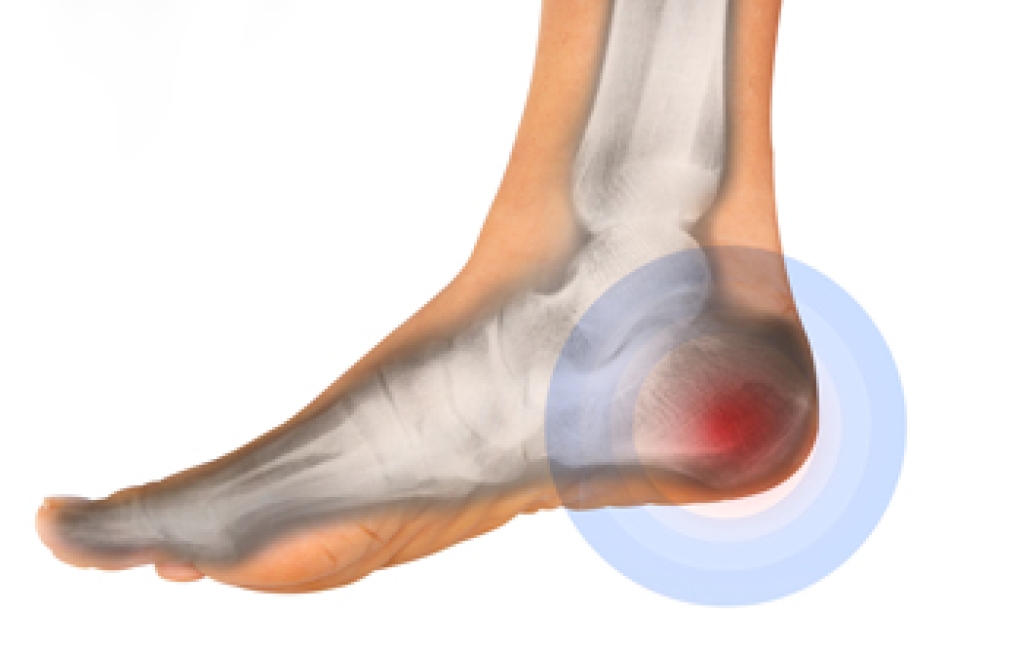

Heel pain is often associated with plantar fasciitis. The plantar fascia is a band of tissues that extends along the bottom of the foot. A rip or tear in this ligament can cause inflammation of the tissue.

Achilles tendonitis is another cause of heel pain. Inflammation of the Achilles tendon will cause pain from fractures and muscle tearing. Lack of flexibility is also another symptom.

Heel spurs are another cause of pain. When the tissues of the plantar fascia undergo a great deal of stress, it can lead to ligament separation from the heel bone, causing heel spurs.

Heel pain should be treated as soon as possible for immediate results. Keeping your feet in a stress-free environment will help. If you suffer from Achilles tendonitis or plantar fasciitis, applying ice will reduce the swelling. Stretching before an exercise like running will help the muscles. Using all these tips will help make heel pain a condition of the past.